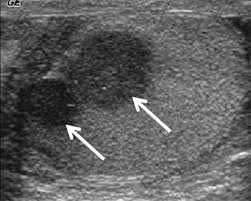

Most testicular cancers in dogs are found through a physical examination by a licensed veterinarian or technician. Some men with testicular cancer have no symptoms at all, and their cancer is found during medical testing for other conditions. Lump or swelling in the. Usually it is not possible for the vet to tell whether an animal has cancer just by looking. Changes in play behaviour, clinical signs of disease and happiness.

The main highways of travel for cancer cells are the bloodstream and the lymphatic system (lymph nodes). Cancer is not a death sentence for your dog. A dog can become lame for many reasons, ranging from a simple sprain or a cut pad all the way to cancer. My dog is 13 years old and is not acting like herself at all so i am concerned if it is cancer that it has already spread. Dogs' noses have as many as 300 million smell receptors , compared to a human's mere 5 million. Blood tests to screen for cancer are still in their infancy. Jack has an aggressive cancer coursing throughout his body. For instance, sometimes imaging tests done to find the cause of infertility can uncover a small testicular cancer. Most of you will never be able to tell whether your dog has testicular cancer or not. Many cancer symptoms in dogs are subtle and can be caused by another condition, but if you notice any of the following potential dog cancer warning signs, it's a good idea to talk to your vet. Cancer treatment has changed radically in the last ten years and more advances are literally happening every day. What to do if you find a bump or lump on your dog: Pets that are cryptorchid are predisposed to the development of sertoli cell tumors and seminomas.

Pin On Dutch Shepherd Dog from i.pinimg.com My vet said it has to be removed to determine if it is cancerous and i do not want to pay $1,000 for no reason. If your dog develops cancer, seeing a veterinarian is the first step in stopping the disease. The american veterinary medical association (avma) reports that one in four dogs will develop cancer at some time in their life and that 50% of pets over the age of 10 will develop cancer. Most of you will never be able to tell whether your dog has testicular cancer or not. Identification of testicular tumors may involve one or all of the following approaches: Take your dog to the vet if it has any lameness, as limping is a sign of pain. Biopsy of the tumor can determine if it is benign or malignant. A dog can become lame for many reasons, ranging from a simple sprain or a cut pad all the way to cancer.

With pets living longer than ever, cancer has become a diagnosis that we see more commonly in older dogs. When we say that test results are normal or negative, commonly the person will let out a breath and say, so my dog doesn't have cancer. well, we don't know that because routine blood panels don't diagnose cancer. Pets that are cryptorchid are predisposed to the development of sertoli cell tumors and seminomas. Finally, weight loss without any other apparent signs of illness is a very important finding and can be an indication of cancer. Sure, we can get clues, but that's often as far as screening tests go. My vet said it has to be removed to determine if it is cancerous and i do not want to pay $1,000 for no reason. If you notice anything unusual, schedule an appointment with your doctor. Some men with testicular cancer have no symptoms at all, and their cancer is found during medical testing for other conditions. Options may include surgical treatment, combination therapy of surgery and chemotherapy, radiation. Hyperestogenism is possible with sertoli cell tumors. Most of you will never be able to tell whether your dog has testicular cancer or not. For instance, sometimes imaging tests done to find the cause of infertility can uncover a small testicular cancer. Biopsy of the tumor can determine if it is benign or malignant.

Though other tumor types are possible, testicular tumors as a whole are generally not aggressive and have a low metastatic rate. The three most common testicular tumors are seminomas, sertoli cell tumors, and interstitial cell tumors. While there are treatments and methods for achieving remission or even curing cancer in dogs, each. Cancer is not a death sentence for your dog. If you notice anything unusual, schedule an appointment with your doctor. The questionnaire identified the three most significant indicators of quality of life in dogs undergoing chemotherapy for cancer: Hyperestogenism is possible with sertoli cell tumors. Some men with testicular cancer have no symptoms at all, and their cancer is found during medical testing for other conditions. Your vet should be able to determine what the cause of the pain is. But if you have any of these signs or symptoms, see your doctor right away. Identification of testicular tumors may involve one or all of the following approaches: First, we get a medical history Finally, weight loss without any other apparent signs of illness is a very important finding and can be an indication of cancer.